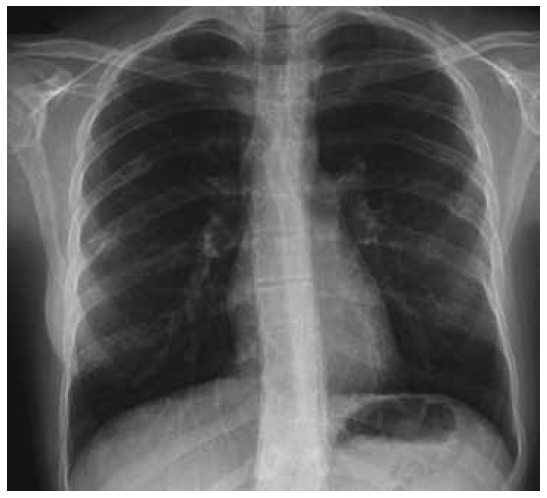

AP radiograph of the thorax showed areas of multiple lucent lesions with bony islands and linear sclerotic changes along the Ribs (Fig. 5). Lateral spine radiograph showed normal vertebral anatomy with no trace of osteogenic lesions (Fig. 6).

Fig. 5. AP radiograph of the thorax showed areas of multiple lucent lesions with bony islands and linear sclerotic changes along the Ribs